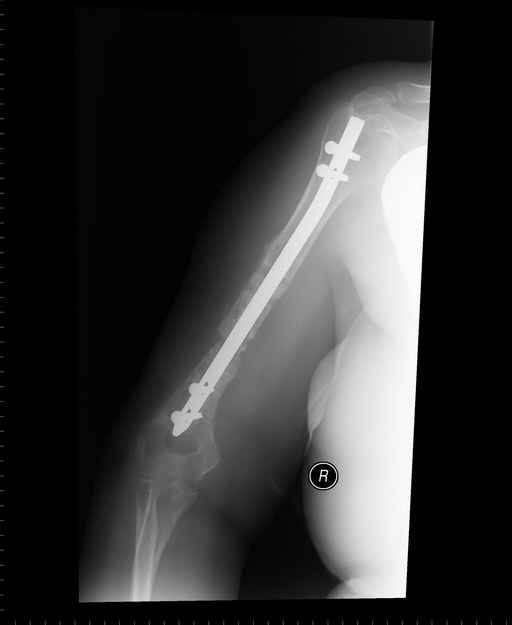

Больная 48 лет, медсестра-массажист, перелом плеча 7 лет назад, оперирована 4-кратно и безуспешно

Больная 48 лет, медсестра. Травма получена 7 лет назад, оперирована первично в Турции - остеосинтез пластиной - несращение - реостеосинтез стержнем там же через год (обычным, с выстоянеием его в полость плеча) - несращение - поступила к нам впервые в марте 2008 года - удаление стержня, реостеосинтез пластиной и костная пластика, в течение 2 лет лизис кости вокруг винтов, смещение фиксатора, в марте 2010 - удаление пластины, реостеосинтез интрамедуллярным стержнем с блокированием (рассверливание + костная пластика). В динамике - вновь лизис в области перелома, нестабильность дистальных блокирующих винтов.